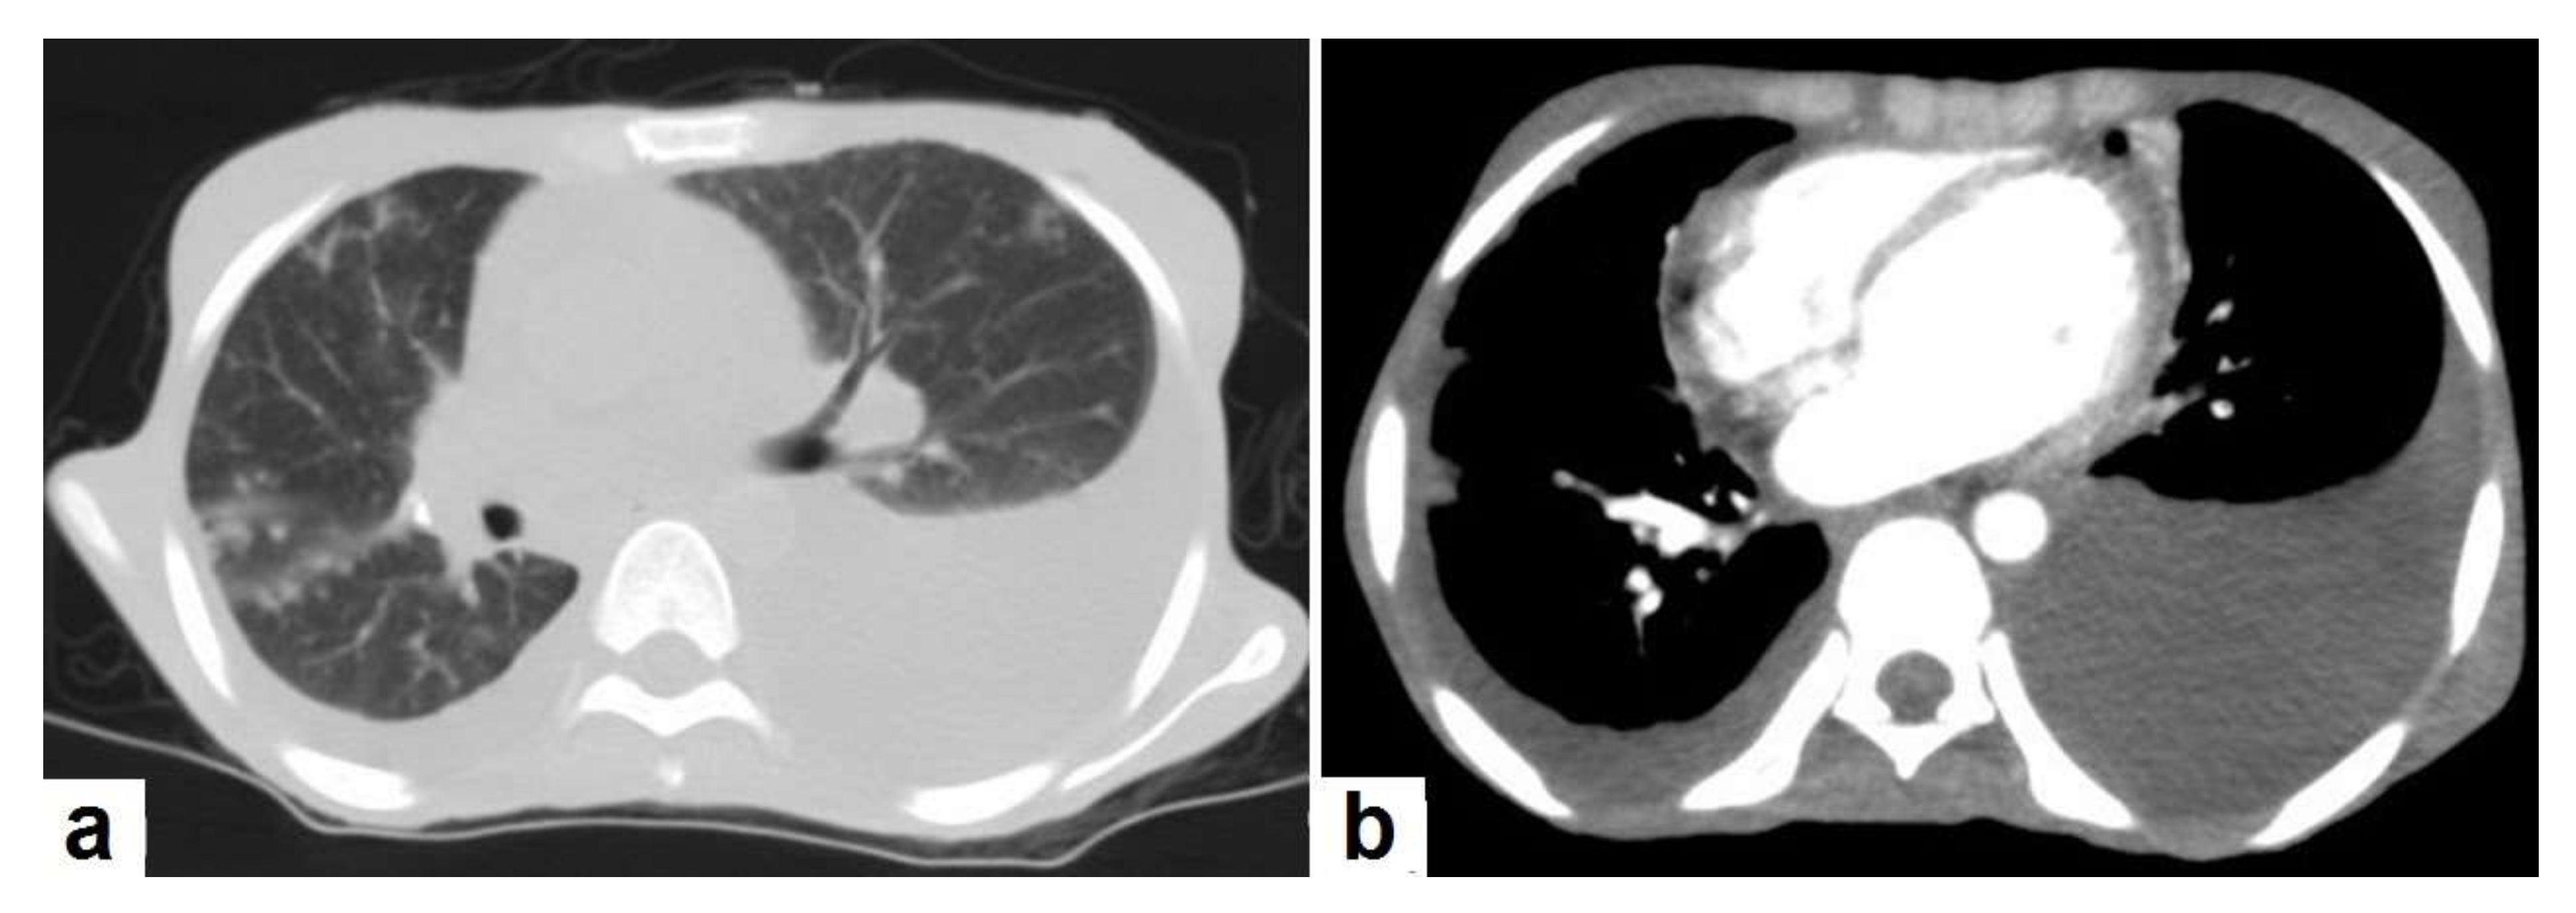

Figure 22. Fibrotic peritonitis in a 20-year-old man with fatigue, abdominal distension, and loss of appetite. Selected axial images of abdominal CT show remarkable omental thickening, forming cake-like masses (arrows) with faint enhancement and mild smooth thickening of peritoneal reflections associated with mild-to-moderate dense ascites and several low-attenuation mesenteric lymph nodes that are challenging to be distinguished from small bowel loops.

• Fibrotic peritonitis (Figure 22) is characterized by remarkable omental and mesenteric thickening forming cake-like masses with bowel loops enlargement and matting that can be seen by CT or ultrasound. [46,47].